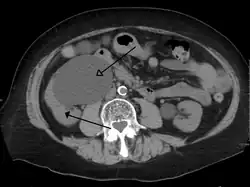

Stone causing hydronephrosis[16]

-